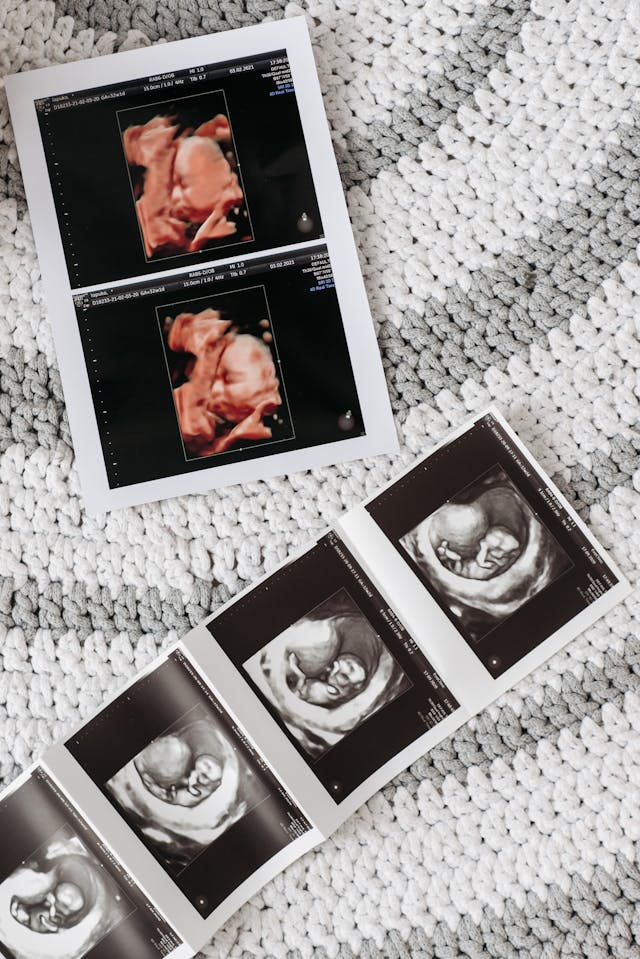

¿Quieres conocer cómo se está desarrollando tu bebé? La ecografía fetal es la solución perfecta para ti. Esta avanzada técnica médica utiliza ultrasonidos para garantizar el normal crecimiento fetal y detectar posibles anomalías. Con el avance de la tecnología, las ecografías 3D y 4D brindan imágenes más detalladas, permitiendo una mejor interpretación y un diagnóstico prenatal de alta precisión, ofreciéndote una visión clara del bienestar de tu bebé.

La ecografía fetal es un procedimiento médico que utiliza ultrasonidos para examinar el desarrollo del feto y detectar posibles anomalías o problemas durante el embarazo. En las últimas décadas, la tecnología ha avanzado, permitiendo obtener imágenes más detalladas y precisas, como las de las ecografías 3D y 4D.

Se utiliza ultrasonidos para crear imágenes del feto, evaluando su crecimiento y desarrollo. Con las ecografías en 3D y 4D, se obtienen imágenes detalladas del bebé, lo que permite detectar alteraciones físicas, malformaciones o problemas relacionados con la oxigenación o nutrición fetal.

Las ecografías 3D y 4D proporcionan imágenes detalladas de la cara, manos, pies y otras características del feto.

Las imágenes 3D y 4D permiten a los padres ver al bebé de manera más realista y cercana.

La ecografía fetal se realiza utilizando un ecógrafo que emite ondas de ultrasonido. Estas ondas rebotan en los tejidos del cuerpo y se capturan para formar una imagen. En las ecografías 3D y 4D, las imágenes obtenidas se procesan digitalmente para ofrecer una visión más completa y detallada del feto.

La ecografía fetal 3D y 4D es una técnica avanzada que permite visualizar el desarrollo fetal y detectar posibles anomalías durante el embarazo. Estas ecografías ofrecen imágenes detalladas que ayudan a garantizar el bienestar del bebé y de la madre. La Dra. Carolina Luque realiza estos estudios, proporcionando un diagnóstico preciso y entregando las imágenes en formato digital o en papel para que los padres puedan conservar este especial recuerdo.